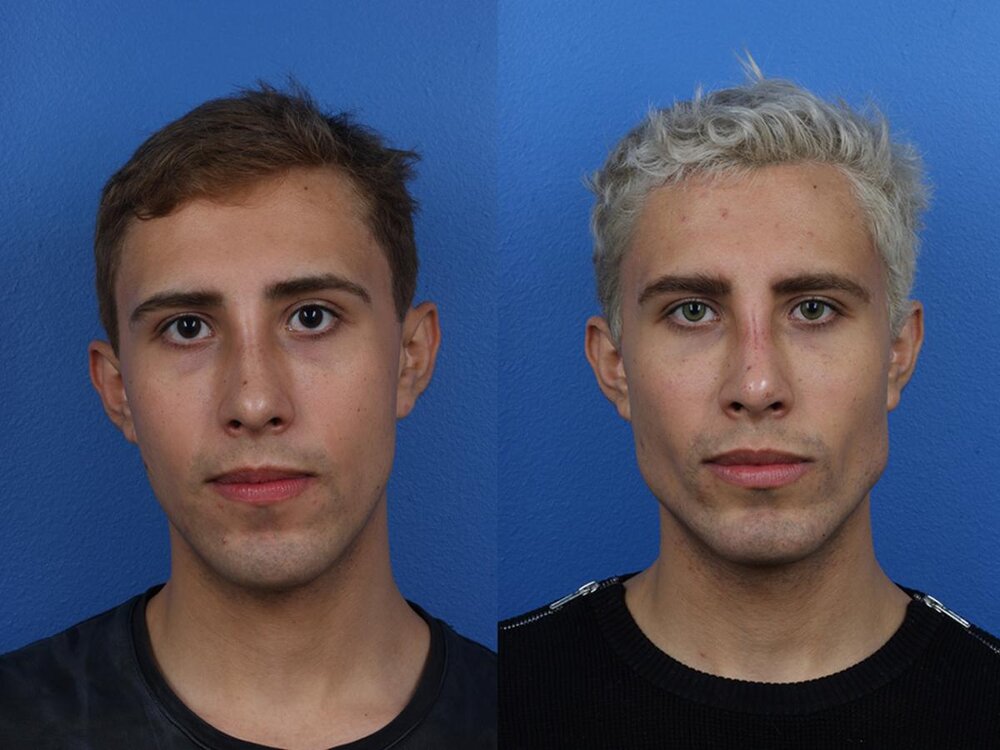

1. Implants *